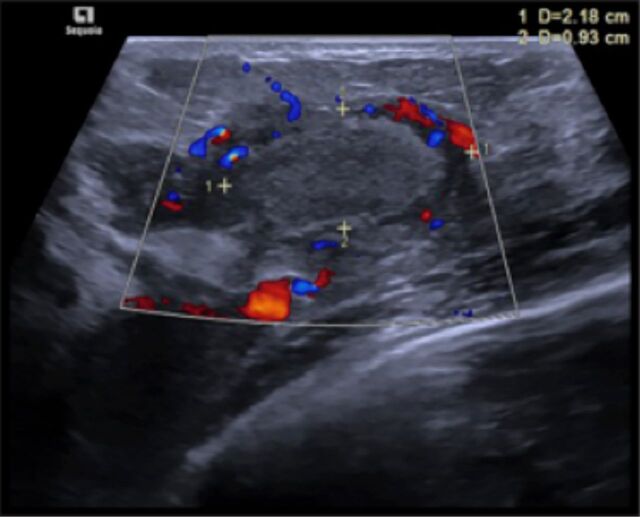

Abstract Image